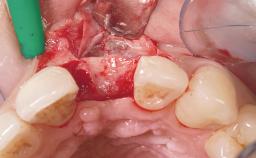

This 43-year-old male patient, a non-smoker, came to our practice because of a fracture of tooth 12 caused by a bicycle accident. Due to the combined para- and infrabony crown and root fracture, tooth extraction, and subsequent implant placement were suggested to the patient as the therapy of choice. The patient had high esthetic expectations with regard to the treatment outcome and asked for an immediate fixed provisional restoration. His individual esthetic risk profile summed up to a medium esthetic risk.

Placement Protocol Immediate implant placement

Loading Protocol Immediate

Provisional Implant-Supported Prosthesis Prosthodontic margin > 3 mm apical to mucosal margin Prosthodontic margin > 3 mm apical to mucosal margin